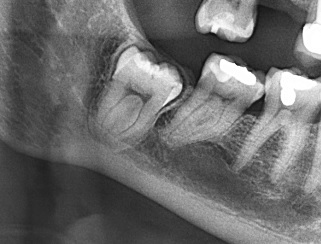

Se muestra la radiografía panorámica de una paciente femenina de 8 años de edad. Se observa la presencia de un defecto de RIPE en el germen dentario de la pieza 44, localización mesial y profundidad dentinal de grado I (figura 4). En la THC adquirida, con un tamaño de vóxel de 0,15 mm, se observó un defecto hipodenso de esmalte y dentina (grado I) ubicado en la vertiente mesial de la cúspide lingual (figura 5).

Se tiene la radiografía panorámica de una paciente femenina de 45 años de edad, en la que se observa un defecto de RIPE en la pieza impactada 48, de localización mesial y profundidad dentinal de grado I, y, además, un segundo defecto ubicado en el centro de la corona y de forma alargada, que sería consistente con una fosa vestibular (figura 8). En la THC adquirida, con un tamaño de vóxel de 0,2 mm, se observó que el aparente defecto de RIPE mesial era, en realidad, la fosa mesiobucal y, además, se encontró un defecto de RIPE, grado I, en la cúspide distolingual asociada a un defecto hipodenso del esmalte adyacente al defecto (figuras 9, 10 y 11).